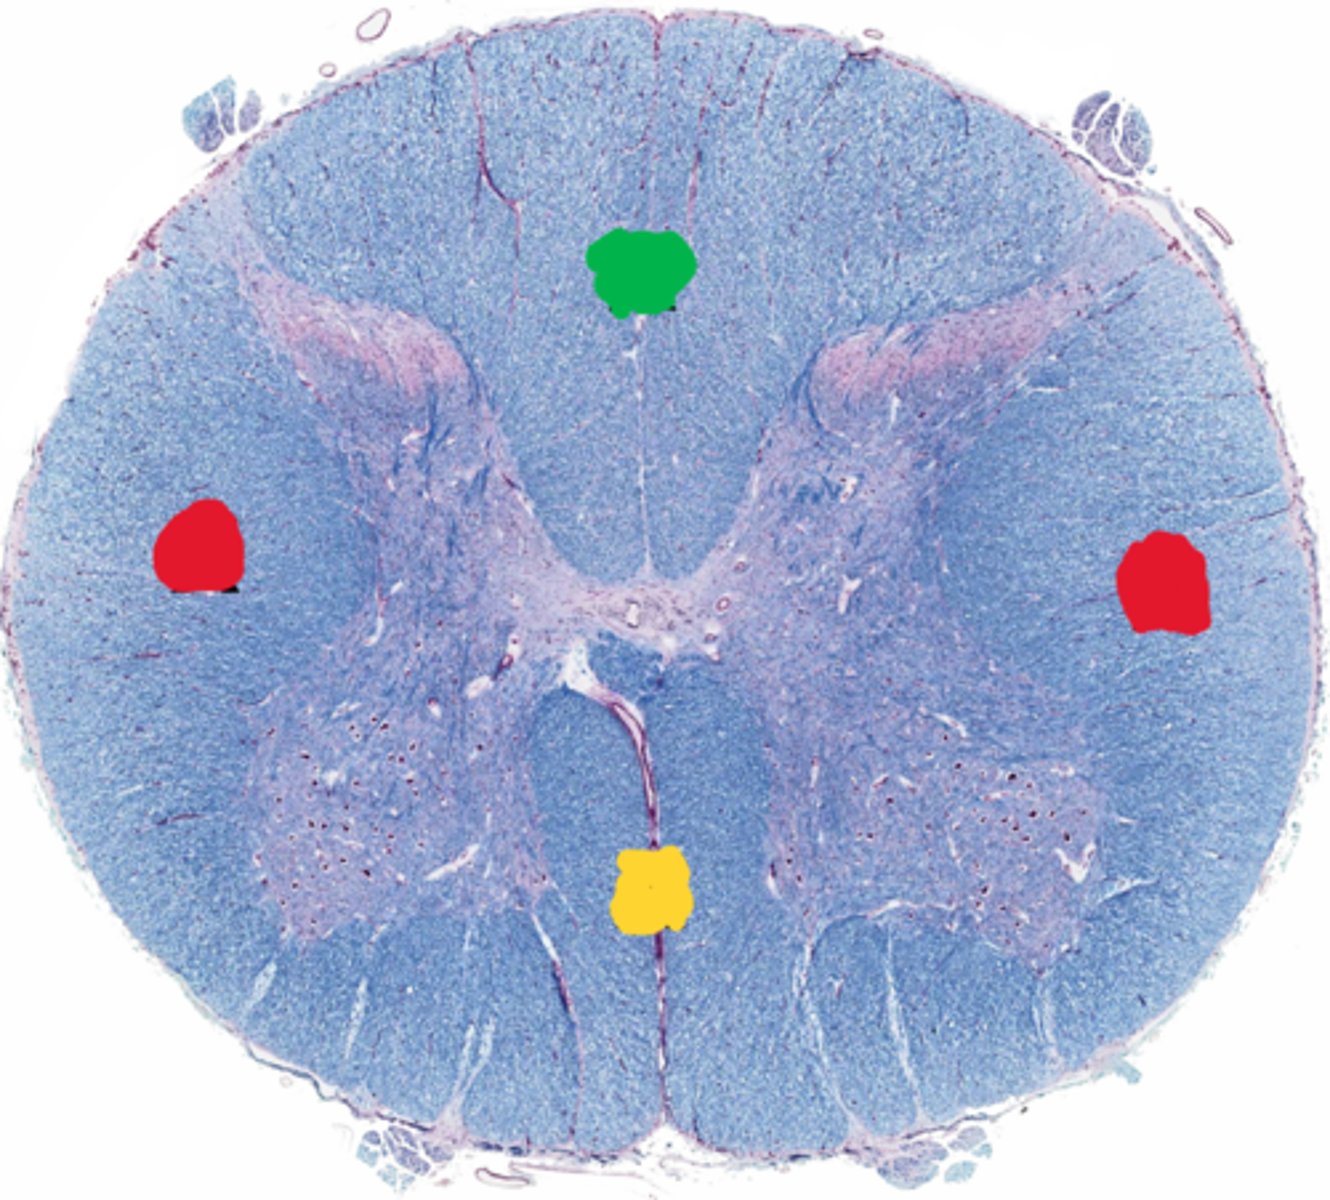

Posterior funiculus

Green

Anterior funiculus

Yellow

Lateral funiculus

Red

Posterior median sulcus

green

Anterior median fissure

red